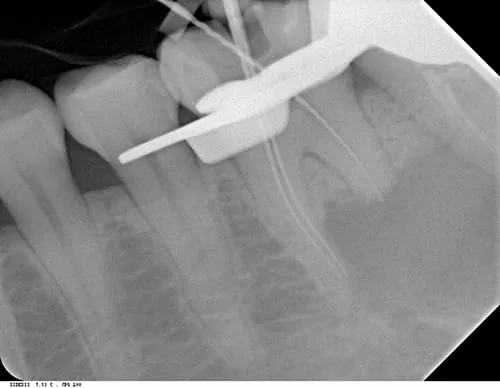

根管治療術中 (左下第一大臼齒)

因此決定配合顯微鏡的使用進行左下第一大臼齒(箭頭處) 根管治療,及左下第二大臼齒(星星處) 重新根管治療,以期病灶縮小後,再進行手術摘除病灶。